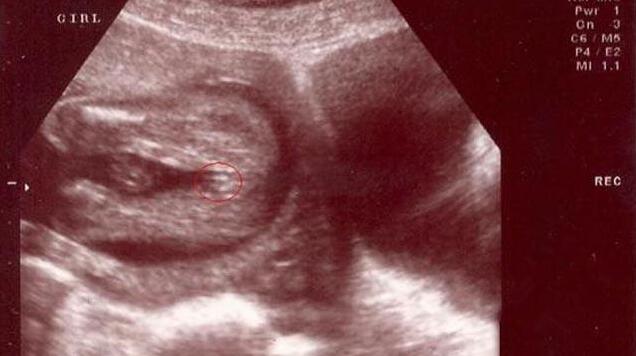

四维彩超女宝宝特征如下

女宝B超图的特征是“三条白线”,当然最好的角度还是从下方来看。如果没有看到三条白线,那么就瞪大眼睛看双腿之间突出的部分,如果特征为两边鼓中间凹,那就基本是女宝了。如下图所示。

三条白线